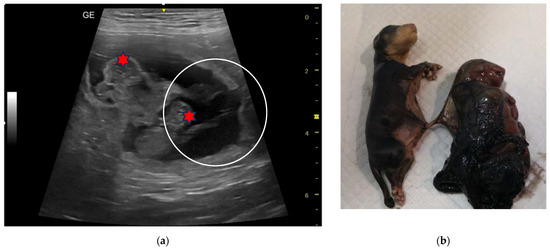

| 6C | 5-year-old Rottweiler female dog | 45 and 55 | 4 | Monochorionic twins, morphologically comparable to the other foetuses; foetal death of the twins. | Natural delivery of two puppies, C-section, and extraction of the twins. | |